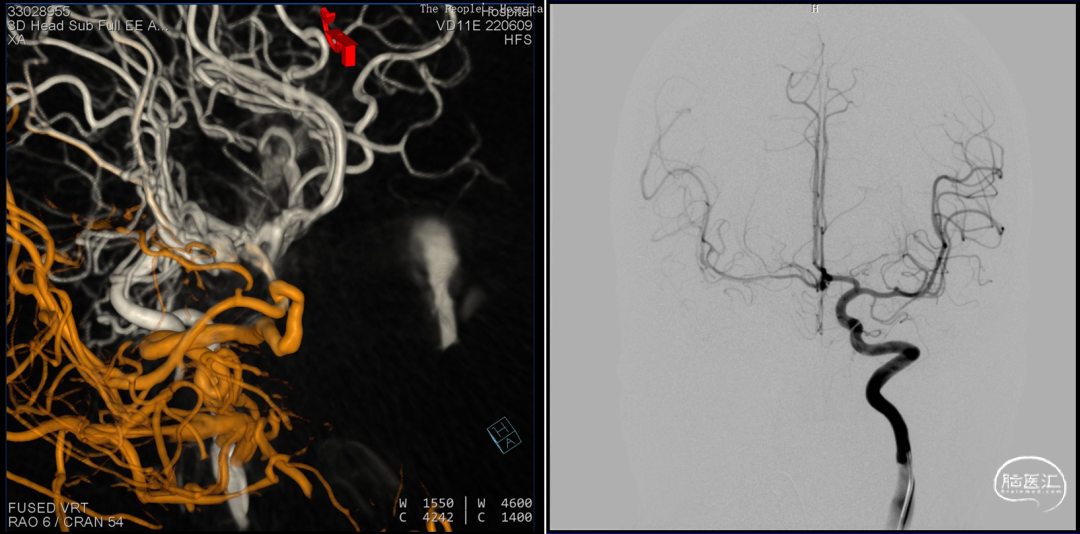

前后循环3d融合寻找假性动脉瘤供血,

考虑为后交通动脉

手术预案

主要诊断:

1.右侧后交通动脉远端假性动脉瘤;

2.SAH (H-H II);

治疗方案:

后交通动脉瘤栓塞术。

策略:

1.球囊辅助;

2.外科胶栓塞 。

难点:

后交通动脉及同侧大脑后动脉保护。